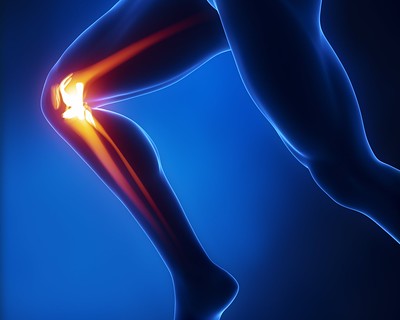

반월판 찢어짐

반월판은 무릎 관절을 완충시키는 연골 조각입니다. 찢어진 반월판은 무릎이 갑자기 비틀리거나 회전하는 결과로 발생할 수 있습니다. 이 부상은 운동선수에게 흔히 발생하며 통증, 부기 및 제한된 이동성을 유발할 수 있습니다.

슬개건염

슬개건염은 슬개골과 정강이뼈를 연결하는 슬개건에 영향을 미치는 과도한 사용 부상입니다. 이 상태는 점프 및 달리기와 관련된 스포츠에 참여하는 운동 선수에게 일반적입니다.